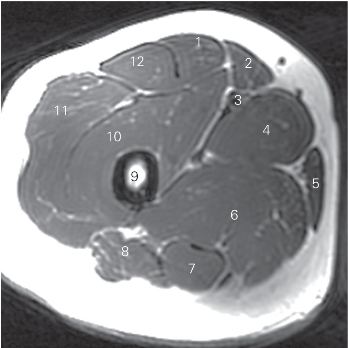

图5-11 经股骨上份的横断层MR T1加权图像

1 股直肌 rectus femoris 2 缝匠肌 sartorius

3 股动、静脉 femoral artery and vein 4 大收肌 adductor magnus

5 股薄肌 gracilis 6 半膜肌 semimembranosus

7 半腱肌 semitendinosus 8 股二头肌 biceps femoris

9 股骨 femur 10 股中间肌 vastus intermedius

11 股外侧肌 vastus lateralis 12 阔筋膜张肌 tensor fasciae latae